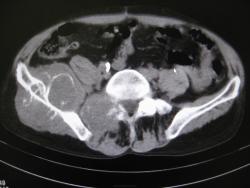

Всем доброго времени суток. Недавно занялся КТ. Вот интересное  наблюдение. Мужчина 40 лет,более полугода боли в тазу, усилились с апреля месяца. Интересно узнать ваши мнения

На мой взгляд, врача, не занимающегося КТ, имеет место злокачественное новообразование с разрушением тазовой кости и частично дуги и тела позвонка. Процесс явно "запущенный", визуализируется несколько узлов. значительных размеров "мягкотканный компонент".

Вот так красота... Не совсем понятен второй узел, у позвоночника справа, но основной, "поедающий" подвздошную кость!... саркомные дела, должно быть.

Предположим саркома Юинга.

При таких размерах и распространении опухоли, ИМХО роль гистологии не очень важна. А может быть позвонок разрушает узел метастатический?

верно. У пациента верифицированный и уже удалённый около года назад рак правой почки.

Гистологию не знаю. Так что 100%-но не скажу. Наиболее вероятный диагноз - мтс в кости таза первичный очаг -рак почки ( гистологию его к сожалению уже не помню). Консилиум наших рентгенологов (до КТ) ставил ОБК под вопросом, фиброзную дисплазию, мтс-маловероятны. С учётом наличия второго очага ОБК исключена ( на ренгенснимках - за поражение крестца убедительно высказаться нельзя), более вероятны мтс (особенно с учётом наличия верифицированного первичного очага -  мтс в кости таза к тому же являются характерными для рака почки)